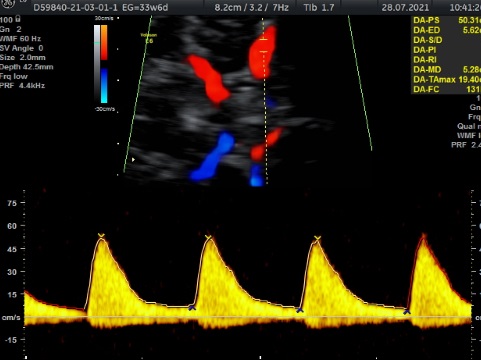

En cualquier semana de embarazo. Es un estudio que nos habla de la oxigenación que esta teniendo tu bebé a través de diferentes flujos sanguíneos ( cordón umbilical, cerebero, arterias uterinas, flujos del corazón. Es un estudio que se realiza para verificar Bienestar Fetal. Tiene una duración de 1 hora y al finalizar el estudio , se realiza 3D, 4D, 5D. Costo $1600